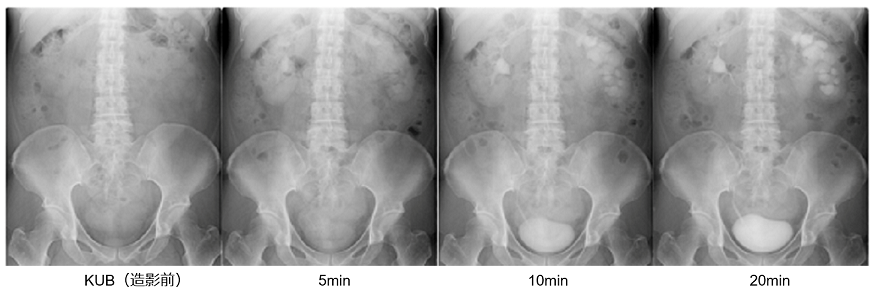

腎盂造影検査(DIP・IVP)

造影剤を用いて、腎臓の機能や尿管結石の有無、血尿の原因などを調べる検査です。普通のエックス線撮影と同じ方法で撮影しますが、造影前・造影剤投与後(5分・10分・20分)と時間を決めて撮影することがほとんどです。必要があれば立位も撮影します。